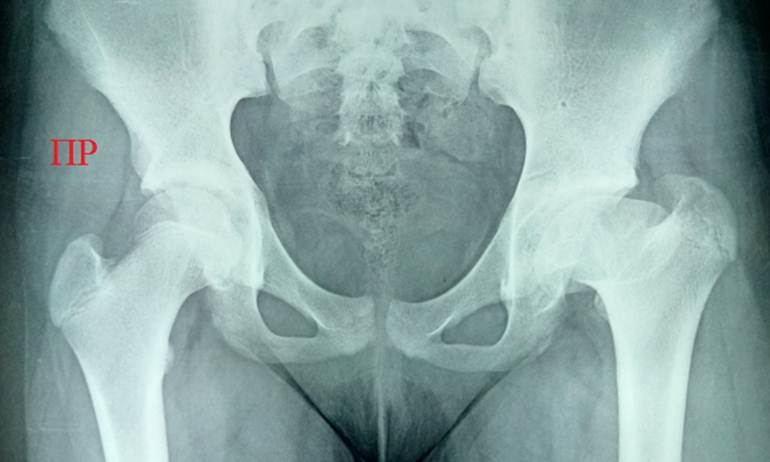

Мальчика

двух с половиной лет привели с жалобами на странный вид ножек и походки. Так

оказалось на самом деле: невысокий и коренастый, он ходил вразвалочку, словно

маленький генерал. Анамнез без особенностей. При осмотре бросились в глаза

непропорционально короткие ноги, загнутые кнутри голени, напоминающие

клюшки, и большое расстояние между

бедрами, отчего тело казалось широким и мощным. Санитарка, ставшая невольной

свидетельницей осмотра, не удержалась и воскликнула: «Ой, какой крепенький

мальчик!» Но мальчик был болен: рентгенография таза показала уменьшение шеечно

– диафизарного угла до 120° слева и 122° справа, показатели вертлужной впадины

в норме. На снимке голеней определяется варусная деформация диафизов

большеберцовой и малоберцовой костей с обеих сторон в их нижних отделах.

Диагноз: двухсторонняя coxa vara.